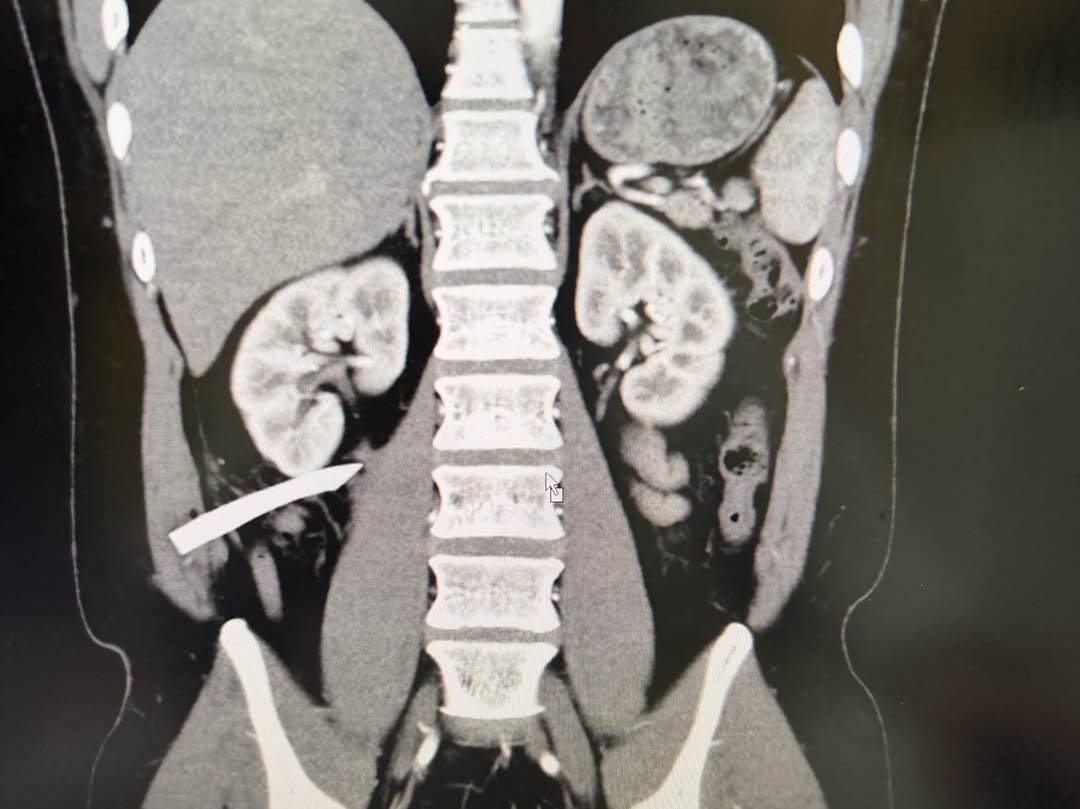

陳聖文表示,原本想趁行程沒那麼繁忙,帶同仁一起密室逃脫,未料壓克力突然破裂,「9公分的碎片直接刺進我的側腹,當場大量出血,緊急送醫處理」。就醫時醫師也指出,碎片已插到腎臟筋膜,距離腎臟相當接近。